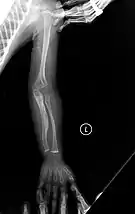

Left forearm

Right forearm

Right femur

Four X-rays of a 24-year-old American man, who had had more than one hundred bone fractures in his lifetime, and received a childhood clinical diagnosis of type IV–B OI. Genetic diagnosis in 2018 identified a previously uncatalogued pathogenic variant in the gene which encodes proα2(I) chains of type I procollagen, COL1A2, at exon 19, substitution c.974G>A. Due to childhood neglect and poverty, subject never received surgery to implant intramedullary rods. Malunions are evident as the humerus and femur were broken in adolescence but orthopedic care did not follow. Severe scoliosis, as well as kyphosis, are also evident. The unavoidably low contrast in the film is due to a combination of subject's obesity and low bone mineral density (BMD). Subject's BMD Z-score was -4.1 according to results of a dual-energy X-ray absorptiometry (DXA) scan also done in 2018.